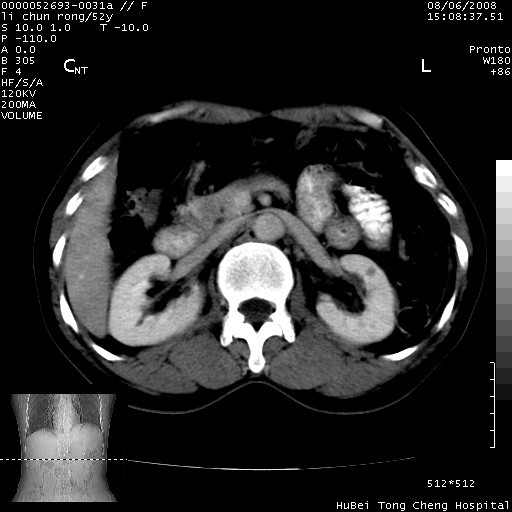

以下是引用云翔在2008-8-7 6:20:00的发言:[br]胰尾部囊性病变,考虑假囊肿,结合实验室检查疾病史

以下是引用zjzjr在2008-8-7 8:38:00的发言:[br]支持胰腺炎伴假囊肿形成,左肾小囊肿.少量腹水.

以下是引用随光逐影在2008-8-7 9:12:00的发言:[br]1)考虑胰腺炎伴假性囊肿形成可能性大;胰腺囊腺瘤待排。2)左肾小囊肿。3)少量腹水。